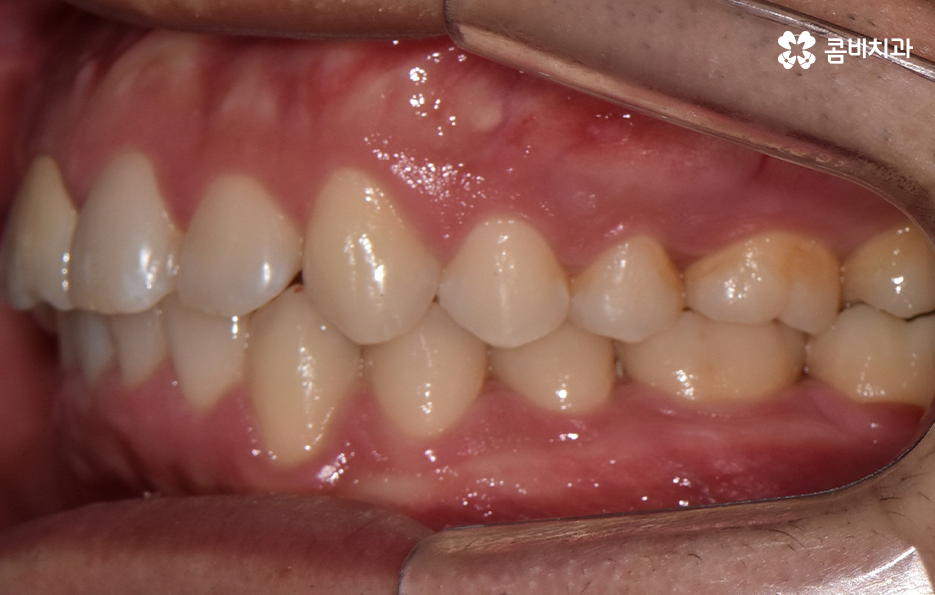

하지만 위에 보시는 환자분의 사례는 윗니와 아랫니의 교합을 고려하고 얼굴형, 골격 등을 고려했을 때도 아랫니만 교정이 가능했던 사례인데 일반적으로 윗니가 아랫니를 살짝 덮고 있어야 하는데 아랫니의 앞니 부분이 유독 안으로 들어와 있었기 때문에 아랫니교정 만으로도 치아교정이 가능했던 사례라고 보시면 좋을 거예요

위 환자분의 사례로 보면 아랫니 중에 하나가 유독 앞으로 튀어나와 있고 나머지 치아는 안으로 들어가 있기 때문에 교합으로 따져볼 때는 아랫니를 전체적으로 앞으로 이동시켜야 했기 때문에 비발치로도 충분히 교정이 가능했고 아랫니교정 만으로도 치료가 가능했어요